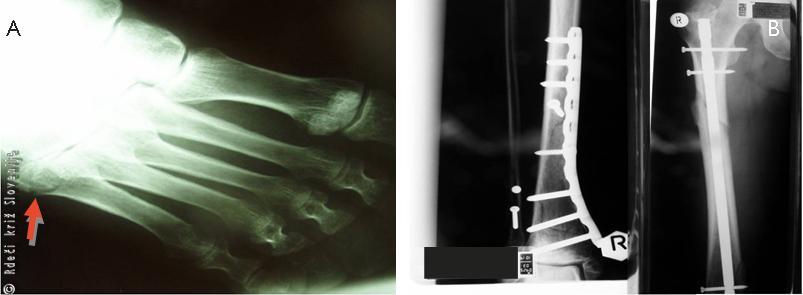

Okrevanje: Bolnik je izvajal lokomotorno fizioterapijo. Kontrolni RTG medenice, desne goleni in stegnenice je pokazal dober položaj fragmentov in osteosintetskega materiala. Zaradi bolečin so opravili RTG desnega stopala, ki je pokazal zlom 5. stopalnice in bližnjega členka četrtega prsta. Ob odpustu v zdravilišče je bil sposoben samostojne hoje z berglami brez obremenjevanja desne noge. Odpustne diagnoze so bile: hemoragični šok, pretres možganov, zlom tretjega do sedmega rebra desno in četrtega do šestega rebra levo, zlom desne stegnenice, zlom desne goleni, zlom sramnice obojestransko, zlom pete stopalnic in prvega členka četrtega prsta desne noge.

Slika 8

A – RTG desnega stopala.

B – RTG zaceljene goleni in stegnenice.